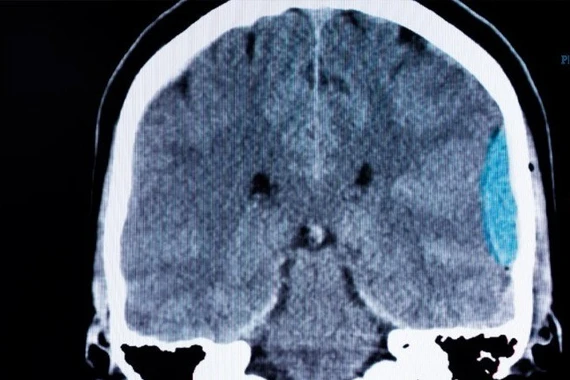

Qua thăm khám lâm sàng và chẩn đoán hình ảnh, các bác sĩ phát hiện bệnh nhân có một khối bã thức ăn lớn trong dạ dày và một khối khác gây tắc ruột non. Trường hợp này phức tạp do tổn thương xuất hiện ở hai vị trí, đòi hỏi chiến lược điều trị phối hợp nhiều chuyên khoa nhằm xử lý triệt để nhưng vẫn bảo đảm an toàn, hạn chế xâm lấn.